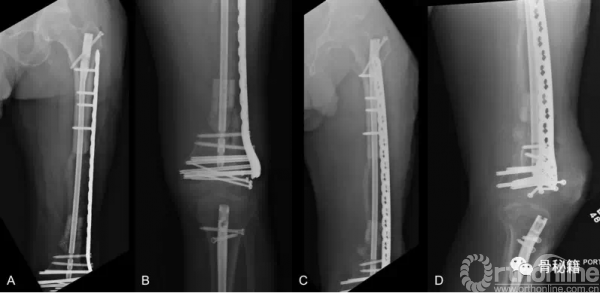

一期进行清创+外固定维持力线和长度+抗生素骨水泥

二期再次清创+骨水泥占位+远端拉力螺钉稳定关节面骨折块

首先,感染控制住了,更换了内固定+磁力髓内钉+一组滑轮

由于远端大量骨缺损,先行了Liss钢板固定远端

同时给与近端股骨磁力髓内钉,同时进行截骨

按照此路径进行了骨延长后,可见骨的生长,截骨块已经延长了一部分

通过漫长的搬移,终于骨折断端接触了

更换全长的髓内钉来进行稳定骨折

术后13个月随访,骨搬移矿化良好